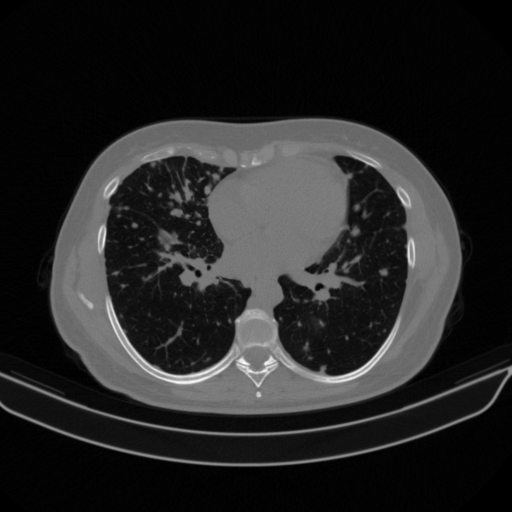

Targeted Slice 70 - Lung Window Analysis (Generated vs Real Venous)

0.752

Lung SSIM

110.9

Lung RMSE

46.5

Lung MAE

Average Lung Window Metrics Across All Slices (133 slices) - Generated vs Real Venous

0.749

Lung SSIM (Avg)

109.7

Lung RMSE (Avg)

44.6

Lung MAE (Avg)

Original NATIVE CT scan (input)

Lung window (WL -600, WW 1500 β†’ Low βˆ’1350, High +150)